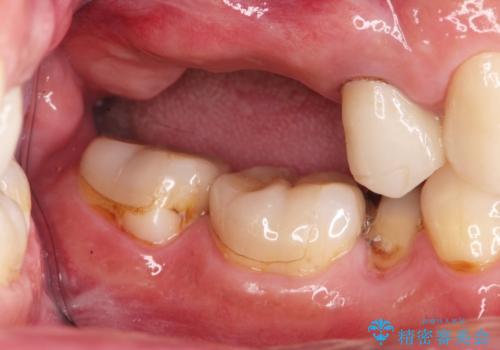

- 歯が抜けてしまい、噛めなくなった右側奥歯の治療を希望され来院されました。

しっかりと咬合機能の回復をするためにインプラント治療を選択されました。

より清掃性の高い、チタン製カスタムアバットメント、審美製・強度に優れるジルコニアインプラントを用いたインプラント治療を計画します。